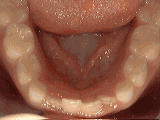

Tratamiento sin frenos

En ocasiones no es necesario usar frenos para mejorar notablemente la alineación de los dientes. Este paciente fue tratado por primera vez a la edad de siete años para corregir el apiñamiento de los dientes inferiores permanentes. El tratamiento consistió en reducir la anchura de los dientes de leche adyacentes, lo cual permitió que los incisivos permanentes se alinearan por sí solos en un periodo de 9 meses.